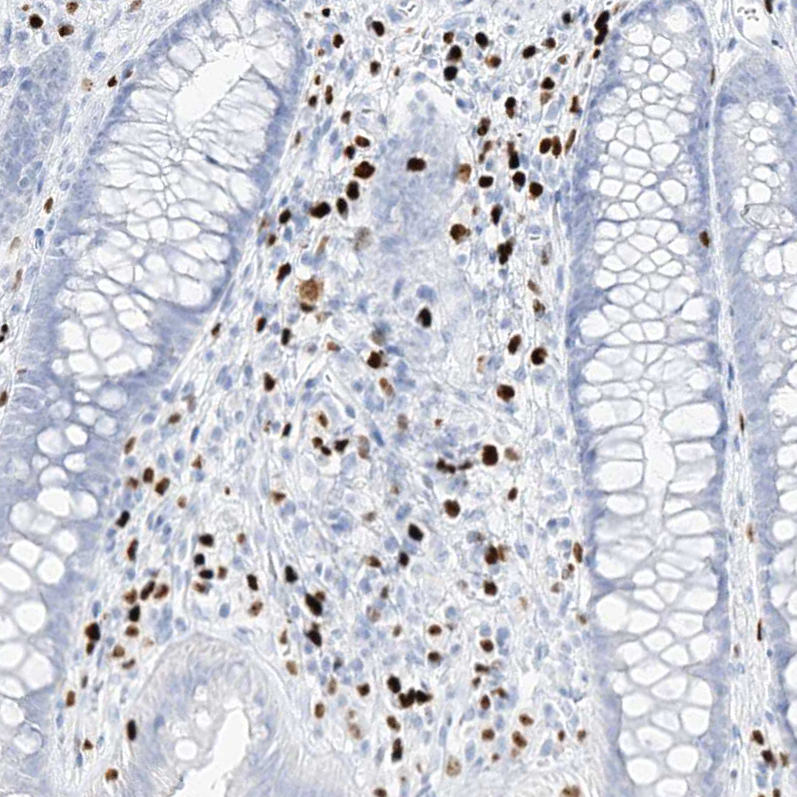

Immunohistochemistry analysis in human lung and skeletal muscle tissues using HPA034532 antibody. Corresponding MNDA RNA-seq data are presented for the same tissues.